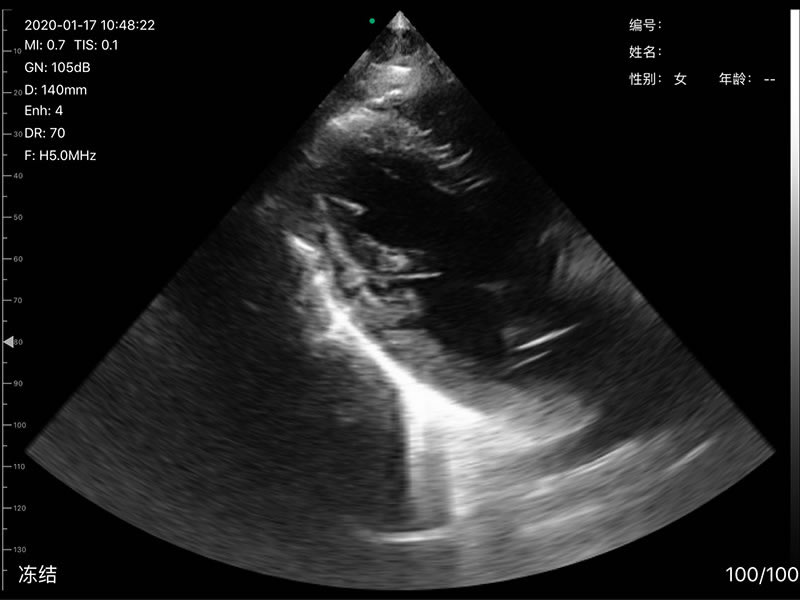

• 探头频率:相控阵2.2/3.6MHz,线阵7.5/10 MHz

• 扫描深度:相控阵90-190mm,线阵 20-100mm,可调

• 显示模式:B、B/M、Color、PW、PDI